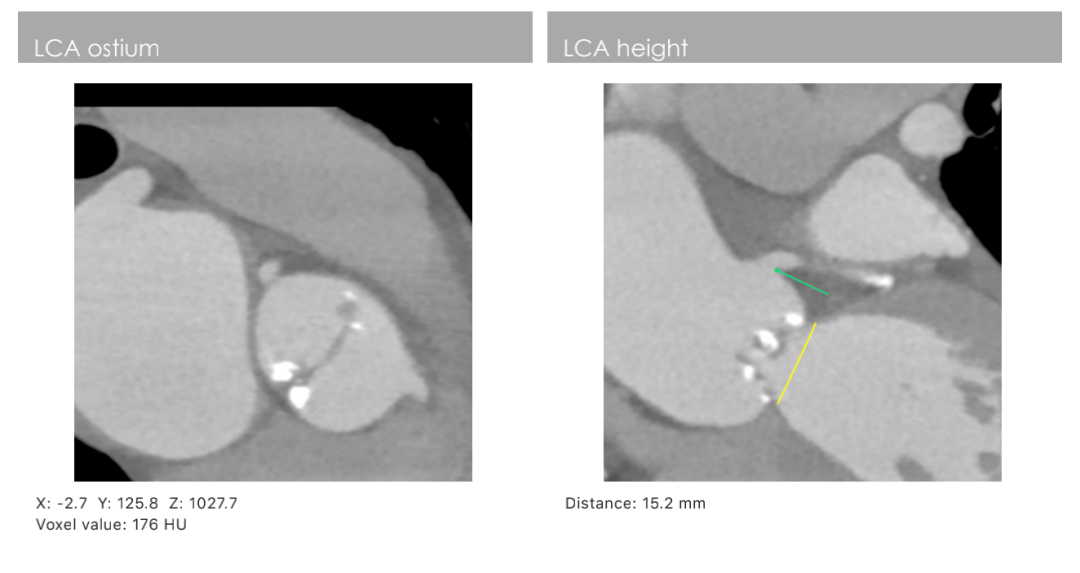

主动脉CT

主动脉瓣环周长79.6mm(平均直径25.4mm),流出道周长87mm(平均直径27.7mm),左冠高度:15.2mm,右冠高度:14mm,主动脉窦宽26.7mm/40.1mm、STJ周长:133.8mm(平均直径42.6mm)高度24.1mm,升主动脉周长:165.5mm(平均直径53mm)。